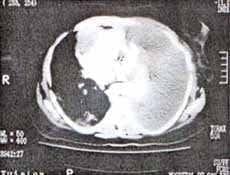

Se realizó TAC de tórax que mostró derrame pleural izquierdo masivo, quiste pericárdico en el nivel de la aurícula derecha e infiltrados alveolares en el pulmón derecho, que tendían a ser nodulares y de localización periférica (Figura 2).

Figura No 2. TAC de tórax en el cual se aprecia imagen sugestiva de quiste pericárdico. Existe además derrame pleural masivo izquierdo e infiltrados alveolares periféricos a nivel de pulmón derecho.

En este caso, desafortunadamente no contamos con autopsia de la paciente, pero se podría especular que se trataba de un angiosarcoma primario de pericardio con metástasis pleuro- pulmonar teniendo en cuenta los hallazgos de la TAC de tórax que mostraba una imagen quística de pericardio a nivel de la aurícula derecha, y el derrame pericárdico observado en el ecocardiograma transtorácico7, 18.